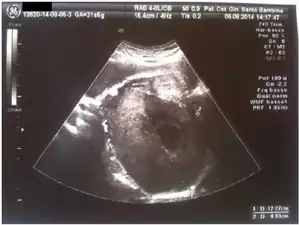

Pregnancy luteoma: ultrasound -